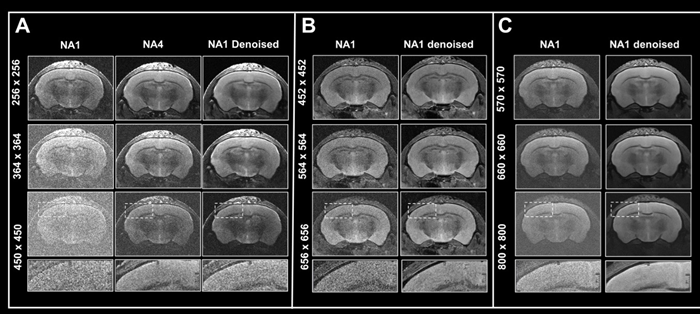

Figure 6. Boosting resolution. Ex vivo T2-weighted TurboRARE data of a fixed mouse head acquired at A) 3 Tesla, B) 7 Tesla, and C) 9.4 Tesla. All images were acquired with 0.8 mm (A) and 0.7 mm (B, C) slice thickness and with a field-of-view of 20 x 20 mm2 and the given matrix size using either no averaging or acquiring 4 averages. Images were reconstructed with no denoising (NA1 and NA4), or after denoising (NA1 Denoised) using a network Large, applying a pre-denoising level of 50 % and denoising level of 70 %. Image Credit: Bruker BioSpin Group

In Fig 6, axial T2-weighted TurboRARE images of a fixed mouse head taken at various field strengths are compared. Images were obtained with a fixed field-of-view of 20 x 20 mm2, slices that were 0.8 mm (3 Tesla) and 0.7 mm (7 and 9.4 Tesla) thick, and changing matrix sizes to produce images with various spatial resolution.

For images acquired at 3, 7, and 9.4 Tesla, the matrix sizes were raised by up to 1.8, 2.6, and 3.1 (compared to the reference protocols' matrix size of 256). These resolution upgrades cause a reduction in SNR for each image.

The loss in SNR can be accounted for by averaging, therefore extra data was collected using four averages.

A comparison of non-denoised averaged images and single averaged images that were denoised demonstrates that denoising reduces increased image noise at higher resolutions and produces images of comparable quality to those generated through averaging.

The advantages in image quality from denoising are greater with data recorded at 3 Tesla, when increasing resolution provides images that are more difficult to interpret, as opposed to data acquired at 7 and 9.4 Tesla, where SNR is naturally higher.

Nonetheless, images taken at 7 and 9.4 Tesla benefit significantly from denoising during reconstruction since the intrinsic higher SNR of these images may be used to pick smaller voxel sizes.

This shows that denoising allows for better resolutions within a given unit time by reducing the requirement for averaging. This can also be useful when averaging is neither desirable nor practical.